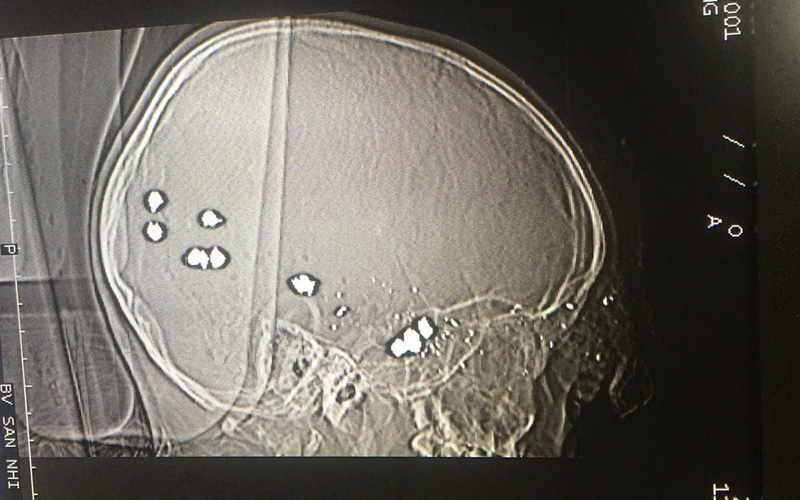

Theo thông tin từ Bệnh viện Sản – Nhi tỉnh Ninh Bình, ngày 29/3, Khoa Cấp cứu tiếp nhận và xử trí bệnh nhi B.T.P. (6 tuổi, trú tại huyện Lạc Thủy, Hòa Bình) trong tình trạng sốc chấn thương giai đoạn mất bù, vết thương thấu não do súng bắn.

Qua khai thác từ gia đình, ở nhà bệnh nhi nghịch súng kíp của gia đình, không may súng cướp cò bị đạn bắn vào đầu. Sau đó, gia đình đưa bệnh nhi đến Bệnh viện huyện Yên Thủy sơ cấp cứu và được chuyển thẳng đến Bệnh viện Sản – Nhi tỉnh Ninh Bình để điều trị tiếp.

Ngay khi tiếp nhận bệnh nhân, các bác sĩ Khoa Cấp cứu nhanh chóng xử trí, hồi sức tích cực, cho bệnh nhi thở máy, thay băng vết thương, mời hội chẩn khẩn cấp.

Tuy nhiên, các dấu hiệu sinh tồn xấu đi, đồng tử giãn, tiên lượng rất xấu và trong tình trạng hết sức nguy kịch.